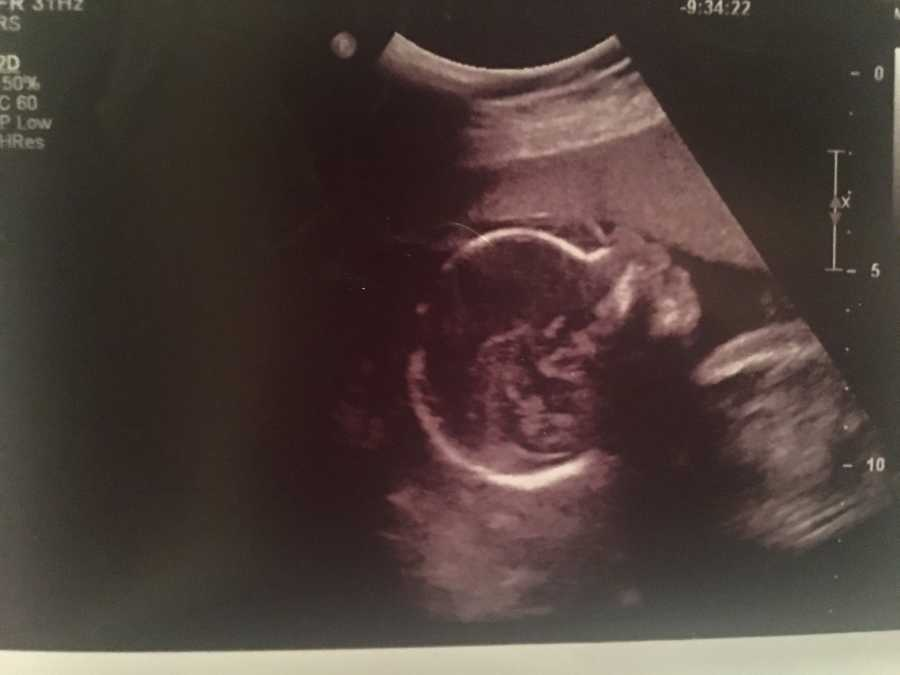

The sonographer smiled politely, the kind of smile that hides worry. Krystalle’s eyes searched the monitor, finding her baby’s heart beating steadily. Relief washed over her for a moment, but it was short-lived. What she didn’t see was the fluid building around her baby’s lungs. That night, instead of celebrating with dinner out, she and her husband sat quietly at the table, their fast food untouched, the air thick with fear.

A few days later, the perinatal specialist confirmed their worst nightmare. The baby girl, whom they would name Gracia, was dying. The fluid had spread everywhere, swelling her tiny body. Only two chambers of her heart were working. The doctor’s voice softened as she explained there was nothing more they could do. Krystalle prayed under her breath, trying to stay present and not collapse under the weight of it all. That night, she clung to a single line looping through her mind: You give and take away; blessed be Your name. It was both a prayer and a plea.